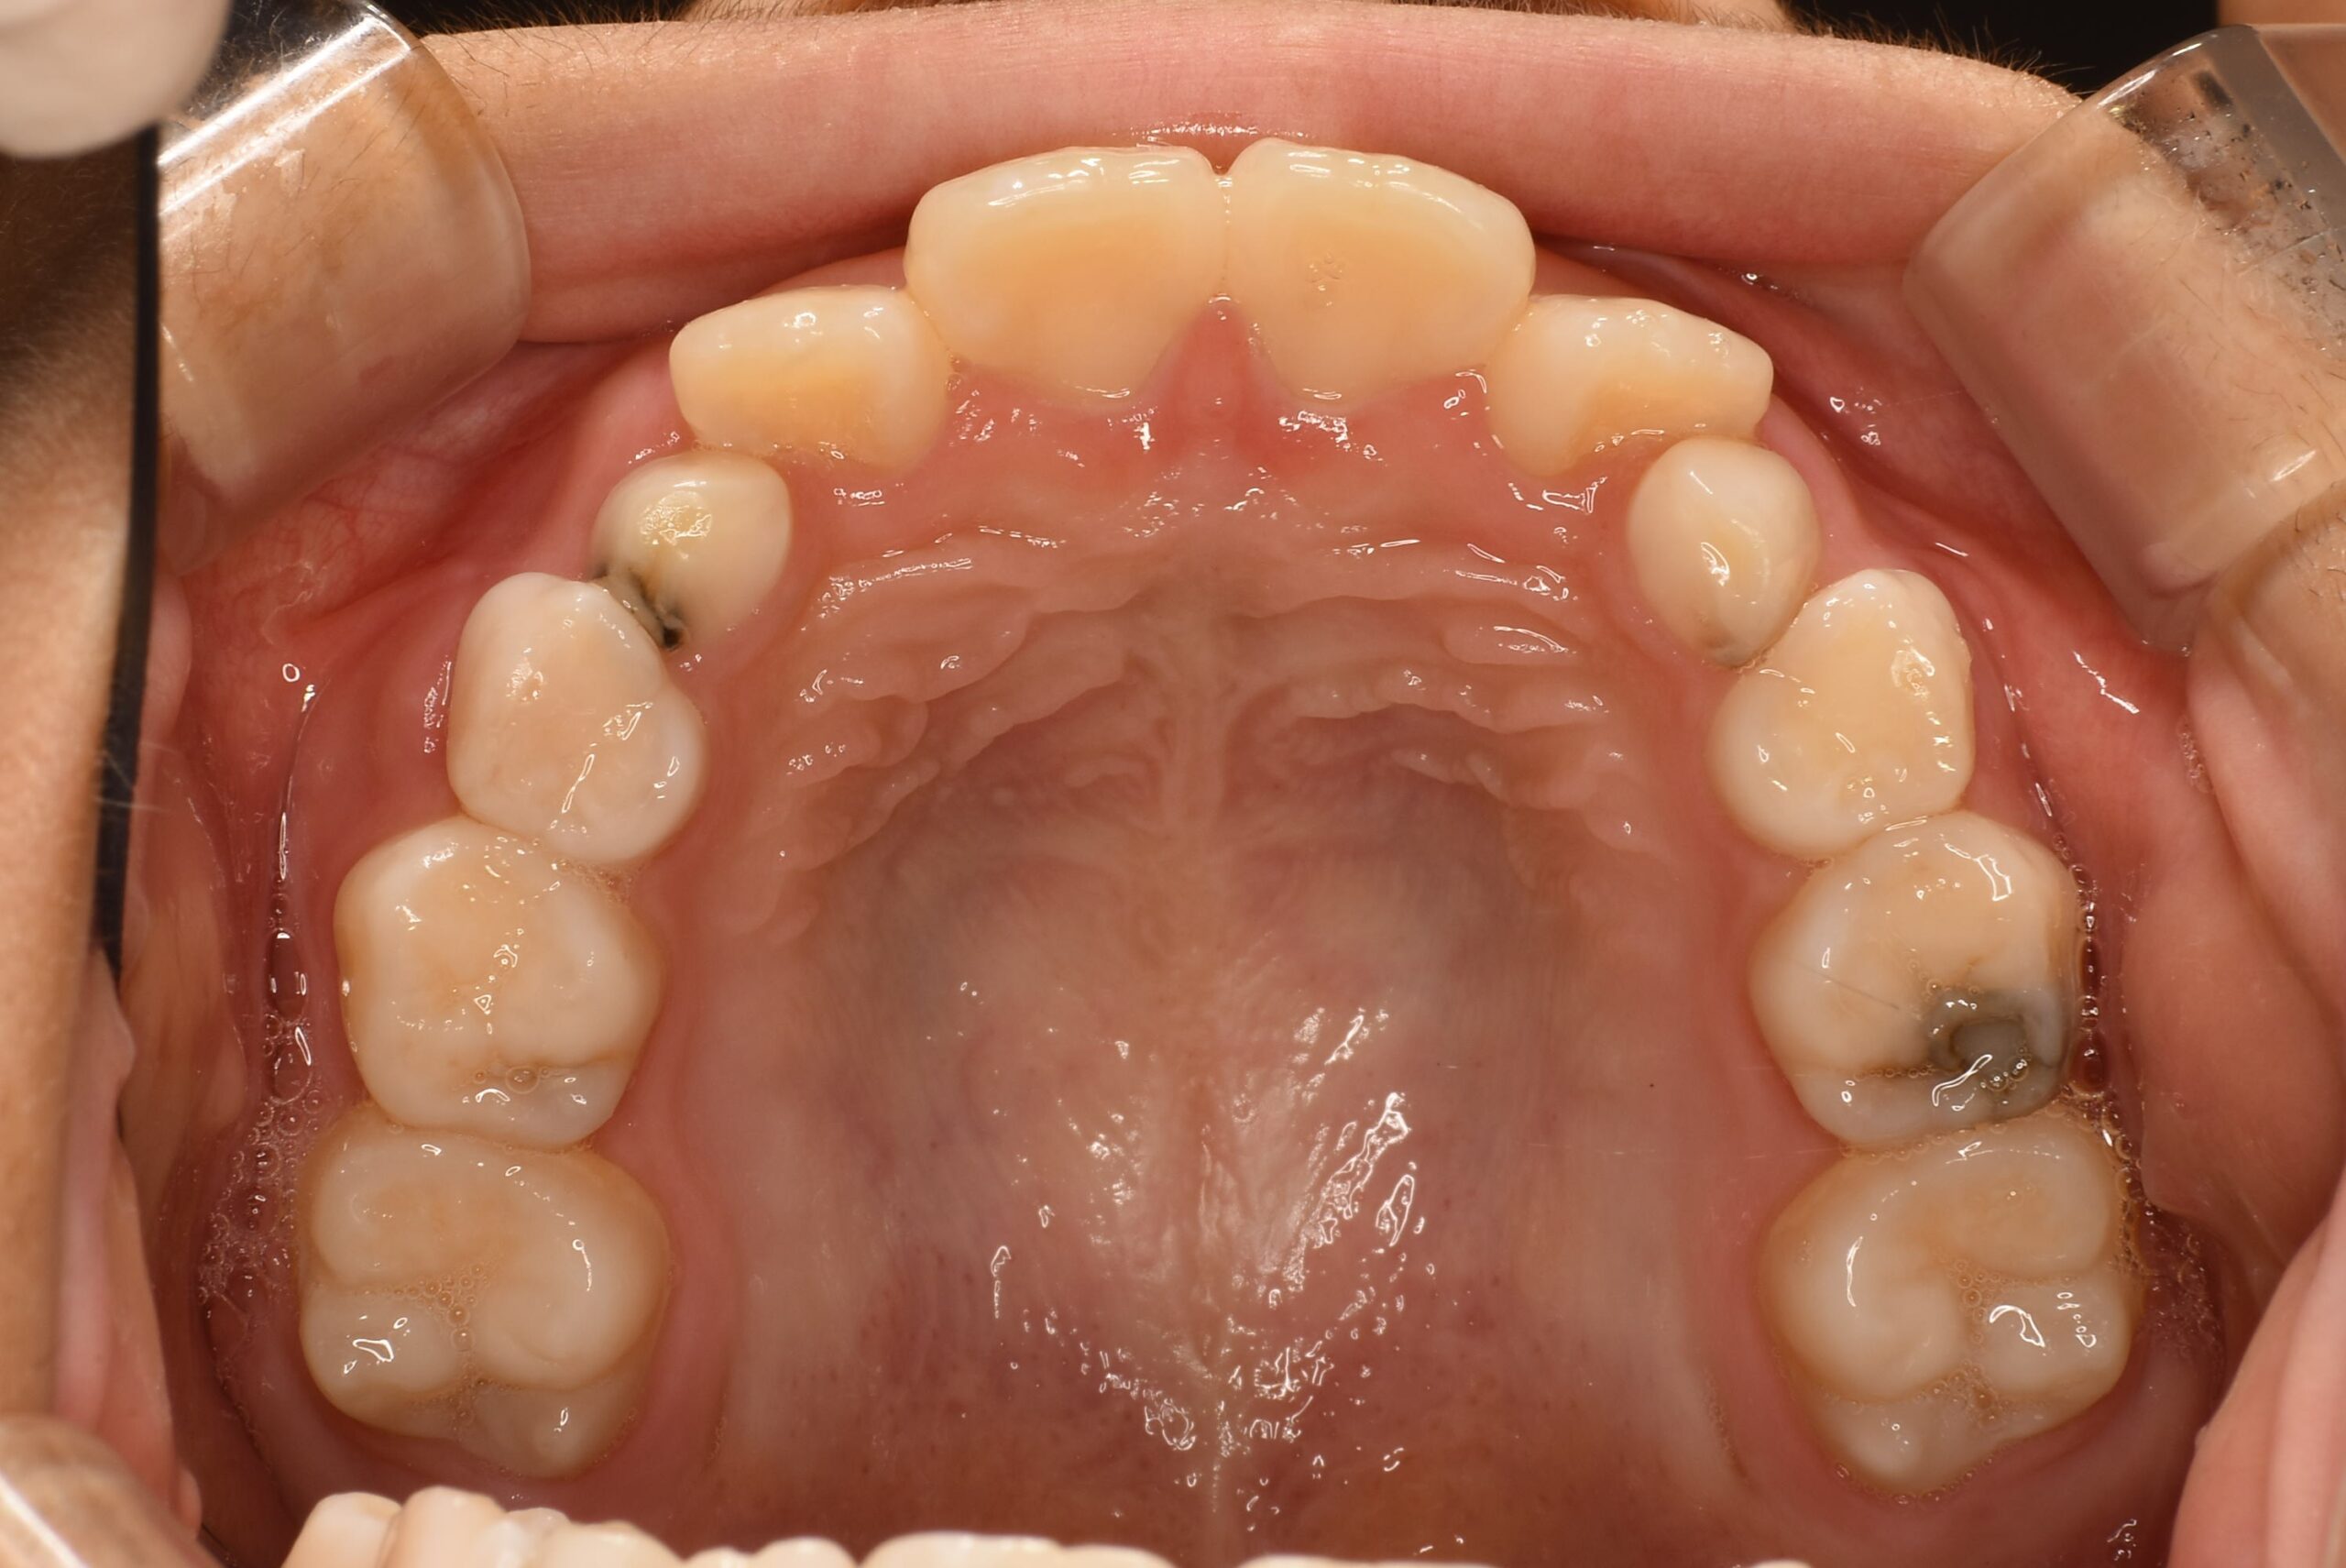

症例詳細:マイオブレースを用いた小児矯正(咬合誘導)

| 主訴 | 出っ歯 |

|---|---|

| 年齢・性別 | 女児・10歳(小学4年生) |

| 診断名 | 上顎前突(出っ歯)、口呼吸および舌の癖 |

| 治療内容 | 日中1時間と就寝時のマウスピース装着に加え、呼吸・舌・飲み込み・唇を鍛えるトレーニング(アクティビティ)を毎日実施。 |

| 治療期間 | 2年2か月(現在も継続中) |

| 費用(税込) | 583,000円 ※検査代・装置代・月1回調整料5,500円含む |

| リスク・副作用 |

|

| 備考 | 本症例は治療途中の経過写真です。治療結果には個人差があります。 |